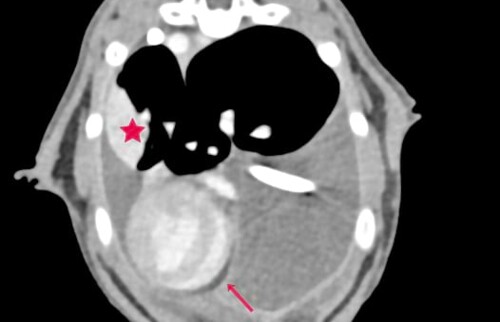

Merlin konnte nach erneuter Thora­ko­zen­tese mittels Thoraxkatheter, Therapiestart mit Rutin, Prednisolon und Buprenorphin zwei Tage lang stabil gehalten werden. Dann zeigte er erneut eine abdominal betonte Tachypnoe mit verschärftem Atem­geräusch. Sonographisch ließ sich ein bilateraler hgr Thoraxerguss sowie eine sehr verdickte und gewebige Pleura darstellen. Diese Befunde konnten in der anschlie­ßenden Computertomographie bestätigt werden, zusätzlich stellte sich der Ln. Sternalis mgr. vergrößert dar und im linken caudalen Lungenlappen war eine struk­tu­relle Veränderung zuerkennen (hypo­attenuierte, intraparenchymal, Kontrastmittel aufnehmend). (Abb. 1-3)

Perikarderguss (Pfeil), strukturelle Lungenveränderung (Stern)

Abb. 1 Perikarderguss (Pfeil), strukturelle Lungenveränderung (Stern)